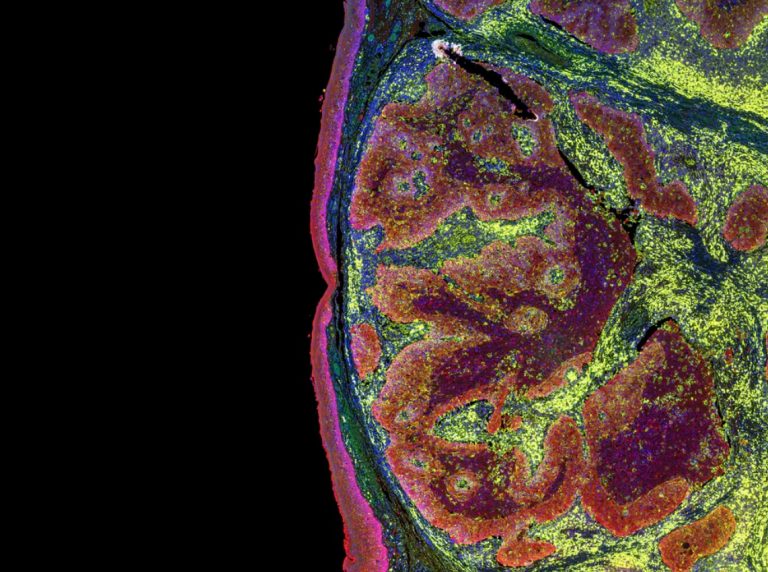

Mesothelioma happens after microscopic fibers found in asbestos are inhaled, which causes pleural mesothelioma. When these fibers are ingested, the result can be peritoneal mesothelioma. Your body cannot expel these fibers, so tumors may form around them.